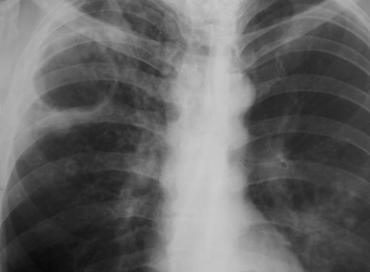

pleureziile medii (cca 1000 ml) – opacitate in menisc, cu limita superioara parabolica concava in sus si inauntru (curba Damoiseau), de intensitate mare, omogena, cu contur sters, ce ocupa baza hemitoracelui. In cazul revarsatelor purulente mai ales, limita superioara a opacitatii lichidiene este rectilinie sau chiar convexa. Cand plamanul de sub revarsat este atelectaziat, curba Demoiseau este inversa (mai inalta medial);

pleureziile mari opacifiaza intreg hemitoracele, la fel ca si revarsatele medii daca examenul este facut in decubit; se constata in plus deplasarea organelor mediastinale si coborarea hemidiafragmului

pleureziile mici se evidentiaza sub forma unei benzi opace de-a lungul grilajului costal doar prin examinarea pacientului in decubit lateral cu raza orizontala.